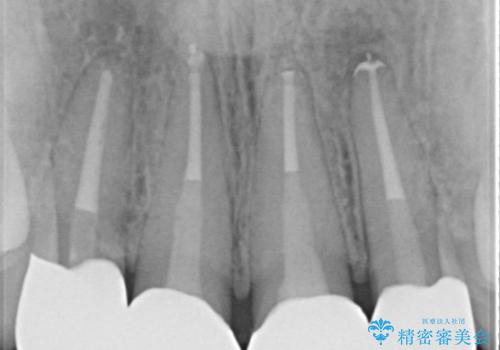

[ 精密根管治療 ] 他院で抜歯しかないと言われた歯を残す